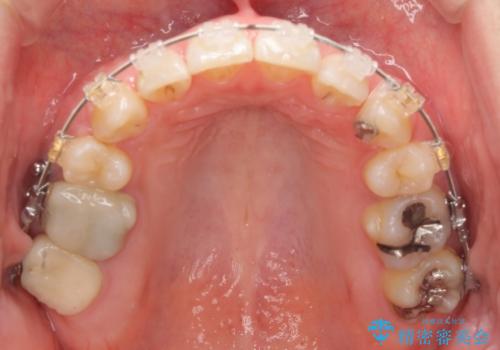

- 矯正装置

- ワイヤー矯正

- 前歯のがたつきを主訴に来院。

前歯のクロスバイト、上の前歯の正中が右にずれていました。

右上の奥歯の高さもない状態でしたが、矯正治療が終わってからしっかりかぶせました。

上下左右の小臼歯を抜歯しています。